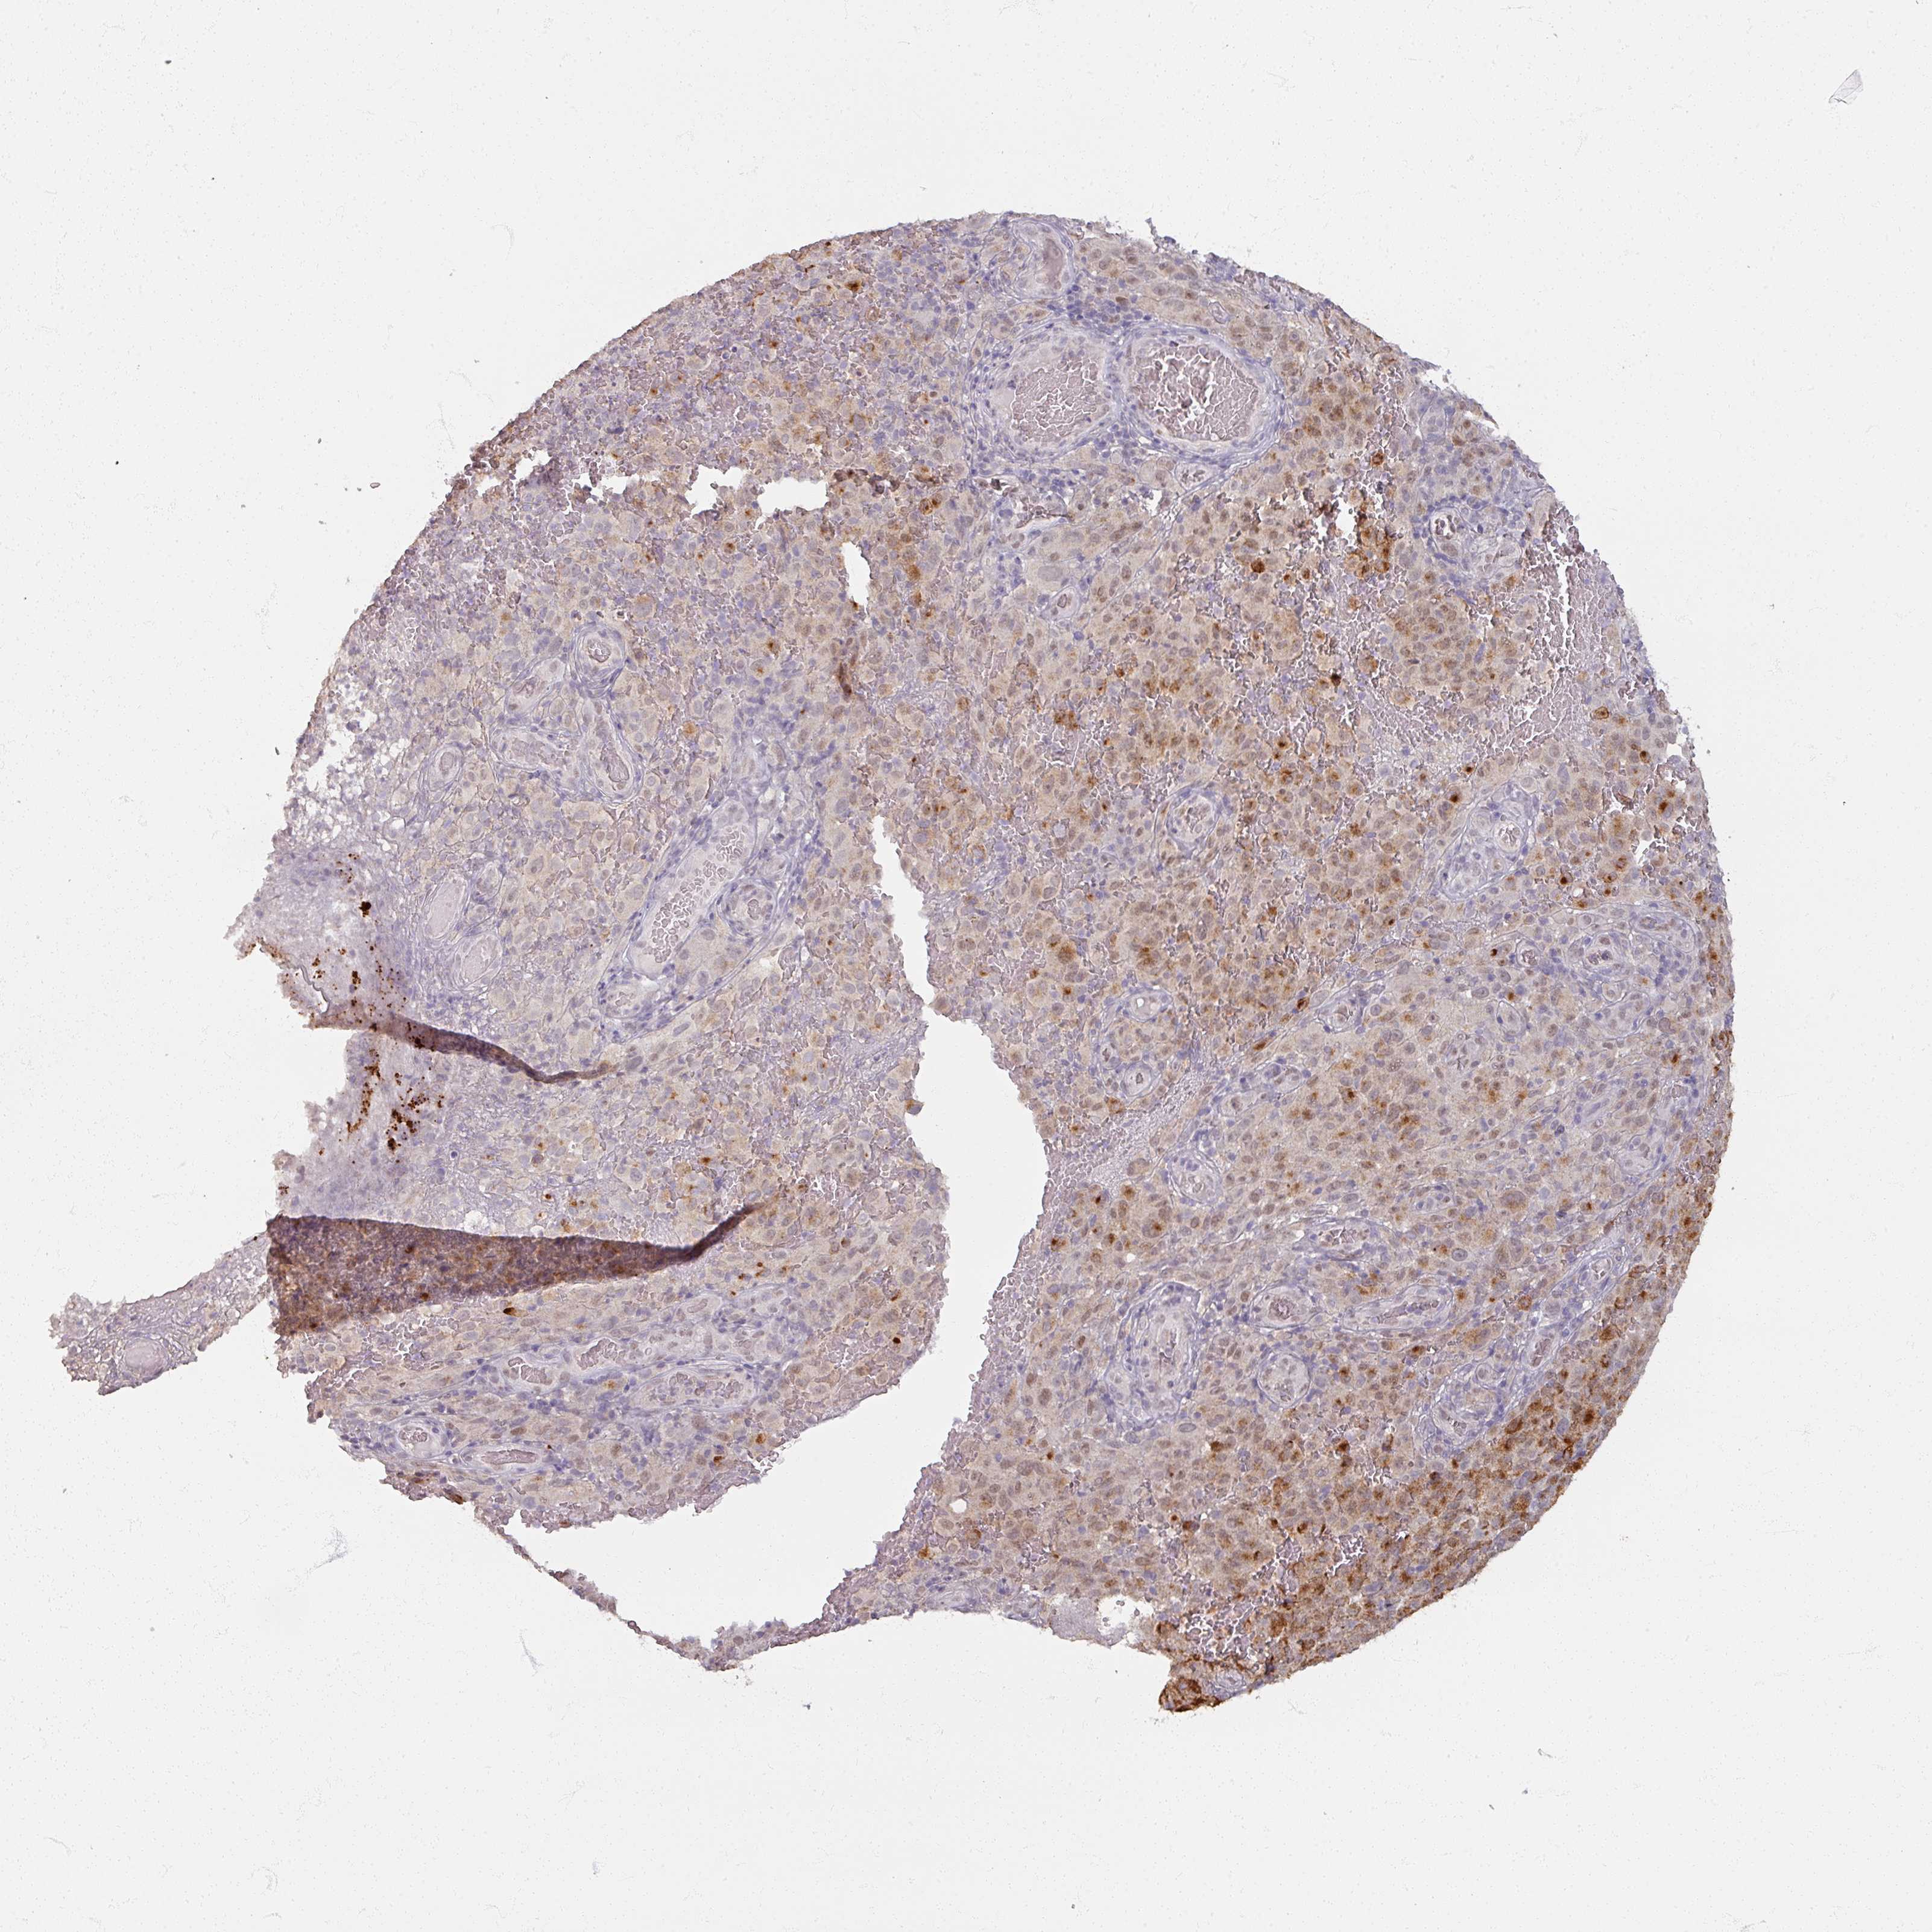

MELANOMA - Protein expressioni

A mouse-over function shows sample information and annotation data. Click on an image to view it in a full screen mode. Samples can be filtered based on level of antibody staining by selecting one or several of the following categories: high, medium, low and not detected. The assay and annotation is described here.

Note that samples used for immunohistochemistry by the Human Protein Atlas do not correspond to samples in the TCGA dataset.

Antibody stainingi

Antibody staining in the annotated cell types in the current human tissue is reported as not detected, low, medium, or high, based on conventional immunohistochemistry profiling in selected tissues. This score is based on the combination of the staining intensity and fraction of stained cells.

Each image is clickable and will lead to virtual microscopy that enables deeper exploration of all samples and also displays staining intensity scores, fraction scores and subcellular localization as well as patient and tissue information for each sample.

Antibody HPA000536

Antibody CAB056152

Antibody CAB056153

Staining

High

Medium

Low

Not detected

Intensity

Strong

Moderate

Weak

Negative

Quantity

>75%

75%-25%

<25%

None

Location

Nuclear

Cytoplasmic/membranous

Cytoplasmic/membranous,nuclear

Malignant melanoma, NOS

Malignant melanoma, Metastatic site